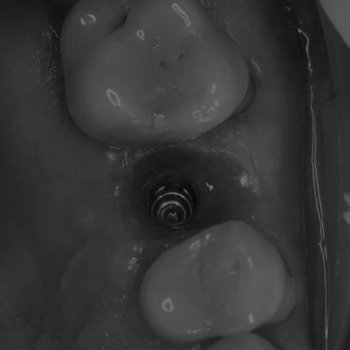

Самец Евгений Евгеньевич

Стоматолог-хирург-имплантолог-пародонтолог

• Дентальная имплантация и коррекция связанных с ней осложнений